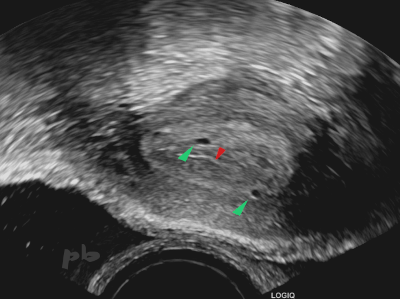

9-GEU

-

Glandes endométriales (►) : petites structures kystiques intra-endométriales, à ne pas confondre avec un sac gestationnel.

-

La ligne hyperéchogène centrale (►) correspond à la cavité utérine.